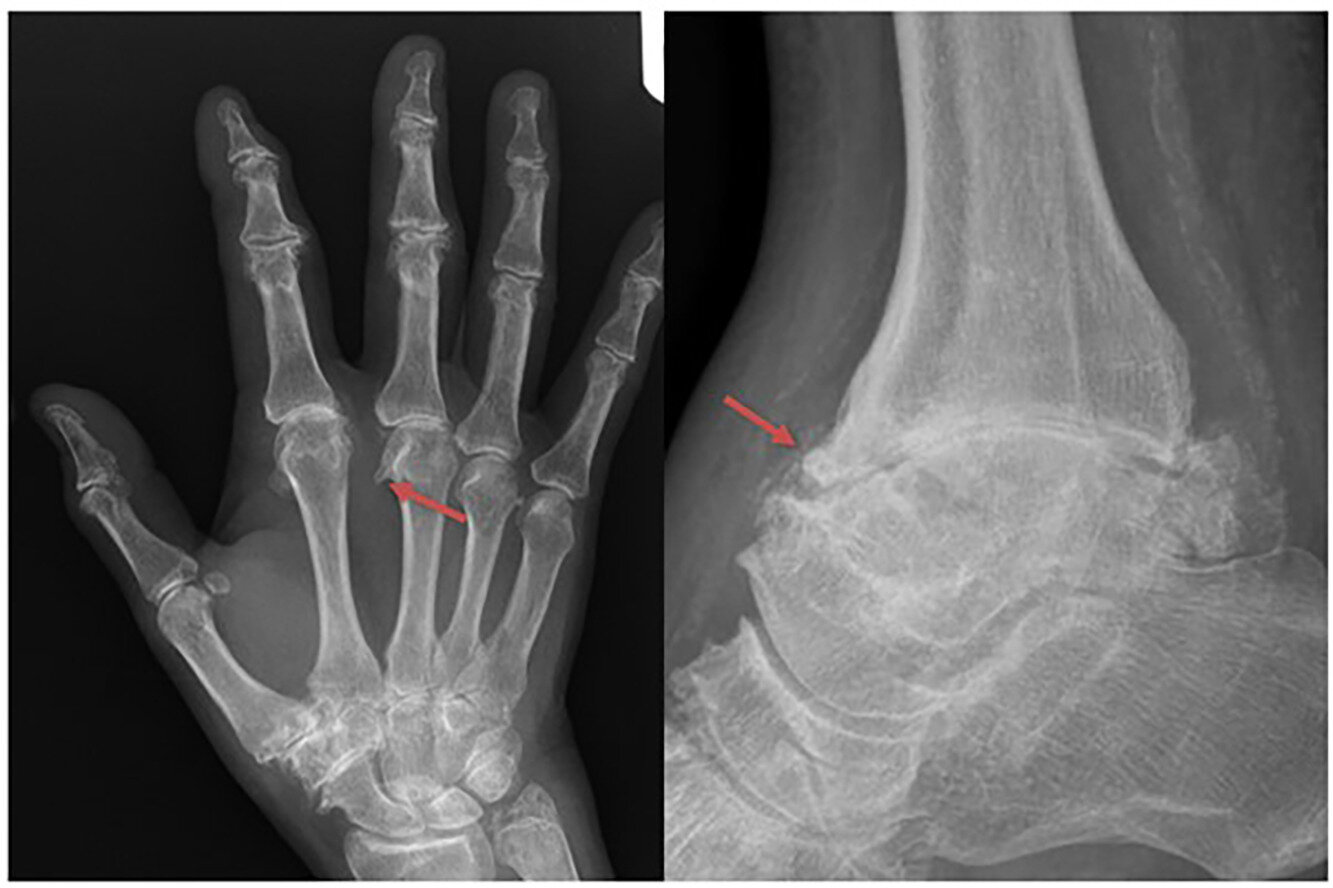

Le résultat a été un modèle de classification basé sur des points qui peut être utilisé chez les personnes souffrant de douleurs articulaires, ainsi que la mutation homozygote HFE C282Y et les preuves antérieures de charge en fer. Le modèle utilise huit variables qui couvrent l’âge au début des symptômes, les caractéristiques cliniques et radiographiques des articulations métacarpo-phalangiennes, interphalangiennes distales et de la cheville, ainsi que les antécédents de chirurgie à la hanche ou à la cheville.

Chacun de ces éléments est facilement évalué dans la pratique clinique de routine et, ensemble, ils sont considérés comme les meilleurs discriminateurs par rapport aux imitations de maladies. Pour atteindre ce seuil, une personne doit obtenir au moins 5 sur 11, sur un minimum de trois critères. Cette approche, qui représente le premier critère de classification destiné à être utilisé dans ce groupe de personnes, offre une spécificité de 93,3 % et une sensibilité de 71,4 % pour la classification en HA.